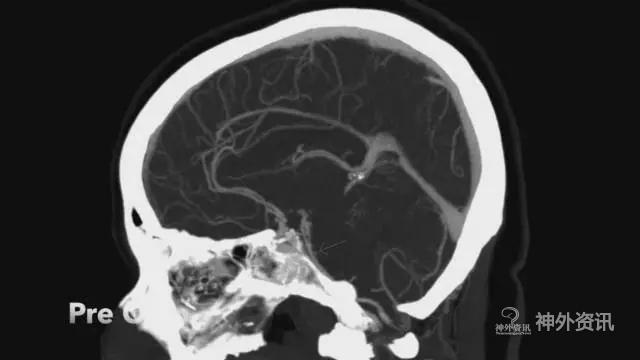

但对于一些特殊类型的BA或SCA,如瘤颈高于后床突1cm以上,就可以采用LSO这种常规简便侵袭性较小的入路(图1、2)。

图1. 破裂的基底动脉尖动脉瘤(瘤颈>后床突1cm)。(注:本文图片均引自芬兰Juha Hernesniemi教授)

图2. 破裂的基底动脉尖动脉瘤(瘤颈>后床突1cm)。